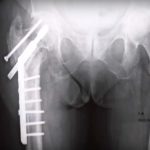

Treatment of Failed Intertrochanteric Fractures

Courtesy: Michael Cross, Hospital for Special Surgery, Ashok Shyam, IORG, OrthoTV